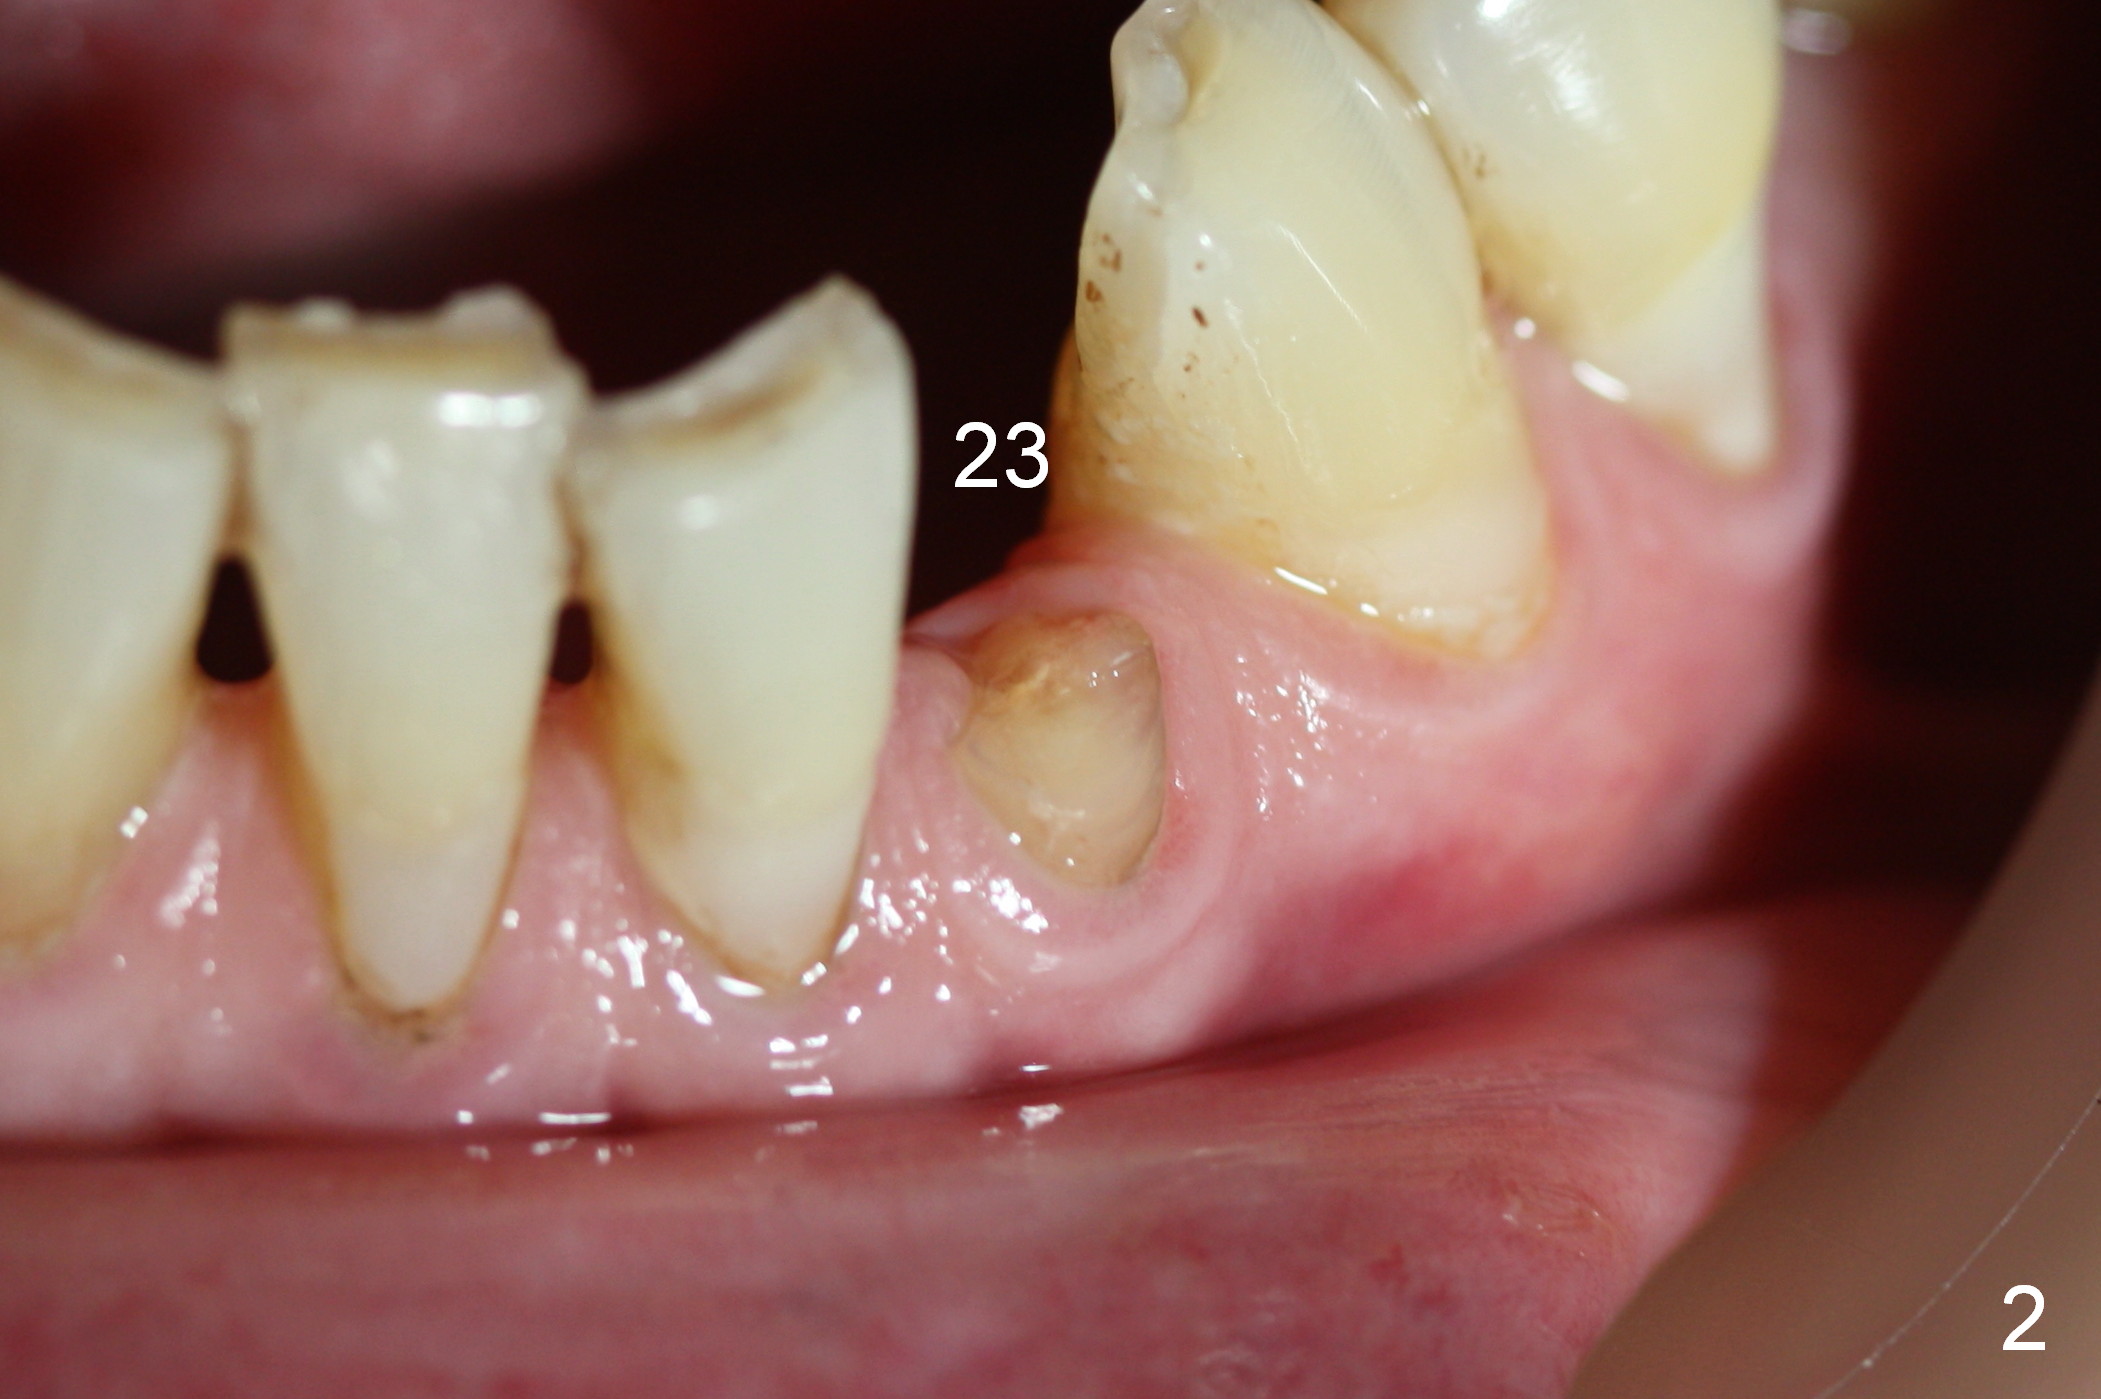

A 74-year-old man has several missing teeth (Fig.1).  His 1st goal is to replace the lower left lateral incisor (Fig.2).  The residual root has an apical lesion (Fig.3 *).  To describe intraop findings, a CT image of a different patient is used (Fig.4 coronal section; B: buccal; L: lingual).  After extraction, the buccal plate is found to be thin and low (Fig.5 arrowheads).  A 1.5 mm pilot drill (Fig.6 red line) is used to initiate osteotomy in the lingual plate of the socket.  Once the drill penetrates the lingual plate, the trajectory changes and the depth is 17 mm from the gingival margin (Fig.7).  A PA is taken (Fig.8); it appears that the osteotomy can be extended more apically.  When the pilot drill extends to 20 mm, there is sudden empty feeling.  The lingual plate has perforated (Fig.9).  A new osteotomy is established buccally (Fig.10 pink).  To avoid buccal plate perforation, especially in the buccal undercut area (>), the coronal end of the drill has to be tilted buccally (<--).  An angled abutment (3x20 mm, 15°) is placed (Fig.11,12).  The abutment is modified (Fig.13,14) to accommodate an immediate provisional (Fig.15,16 P).  Perio dressing is to be applied to prevent the bone graft from getting dislodged buccally (Fig.15).  The dressing is in place 7 days postop (Fig.17).